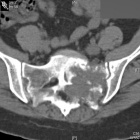

L.T. - 53 year old woman with left lower extremity and pelvic pain for two months

Zoom image: Radiological image Radiological image.

Zoom image: Cell stain Cell stain.